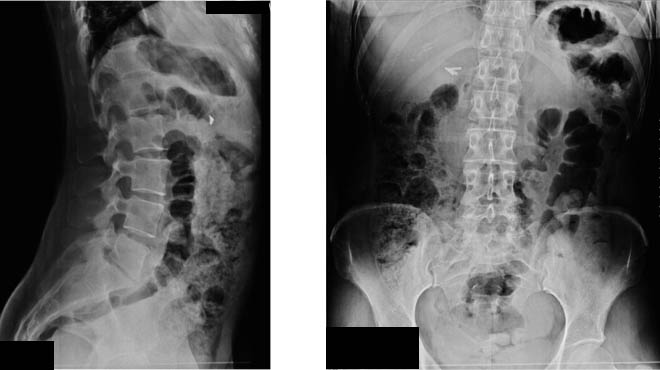

Le moderne tecniche mini-invasive a “doppio approccio combinato” laterale e posteriore sono un esempio in chirurgia vertebrale che permette di trattare la discopatia degenerativa a 360° gradi, rispettando la muscolatura, conservando la sua funzione e ricostruendo la lordosi lombare, che in questa patologia è spesso notevolmente ridotta.